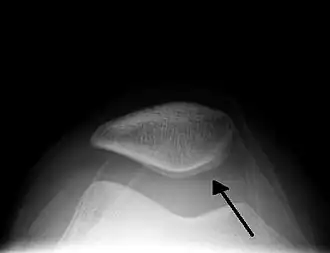

Skyline view of the patella demonstrating a large joint effusion as marked by the arrow. -